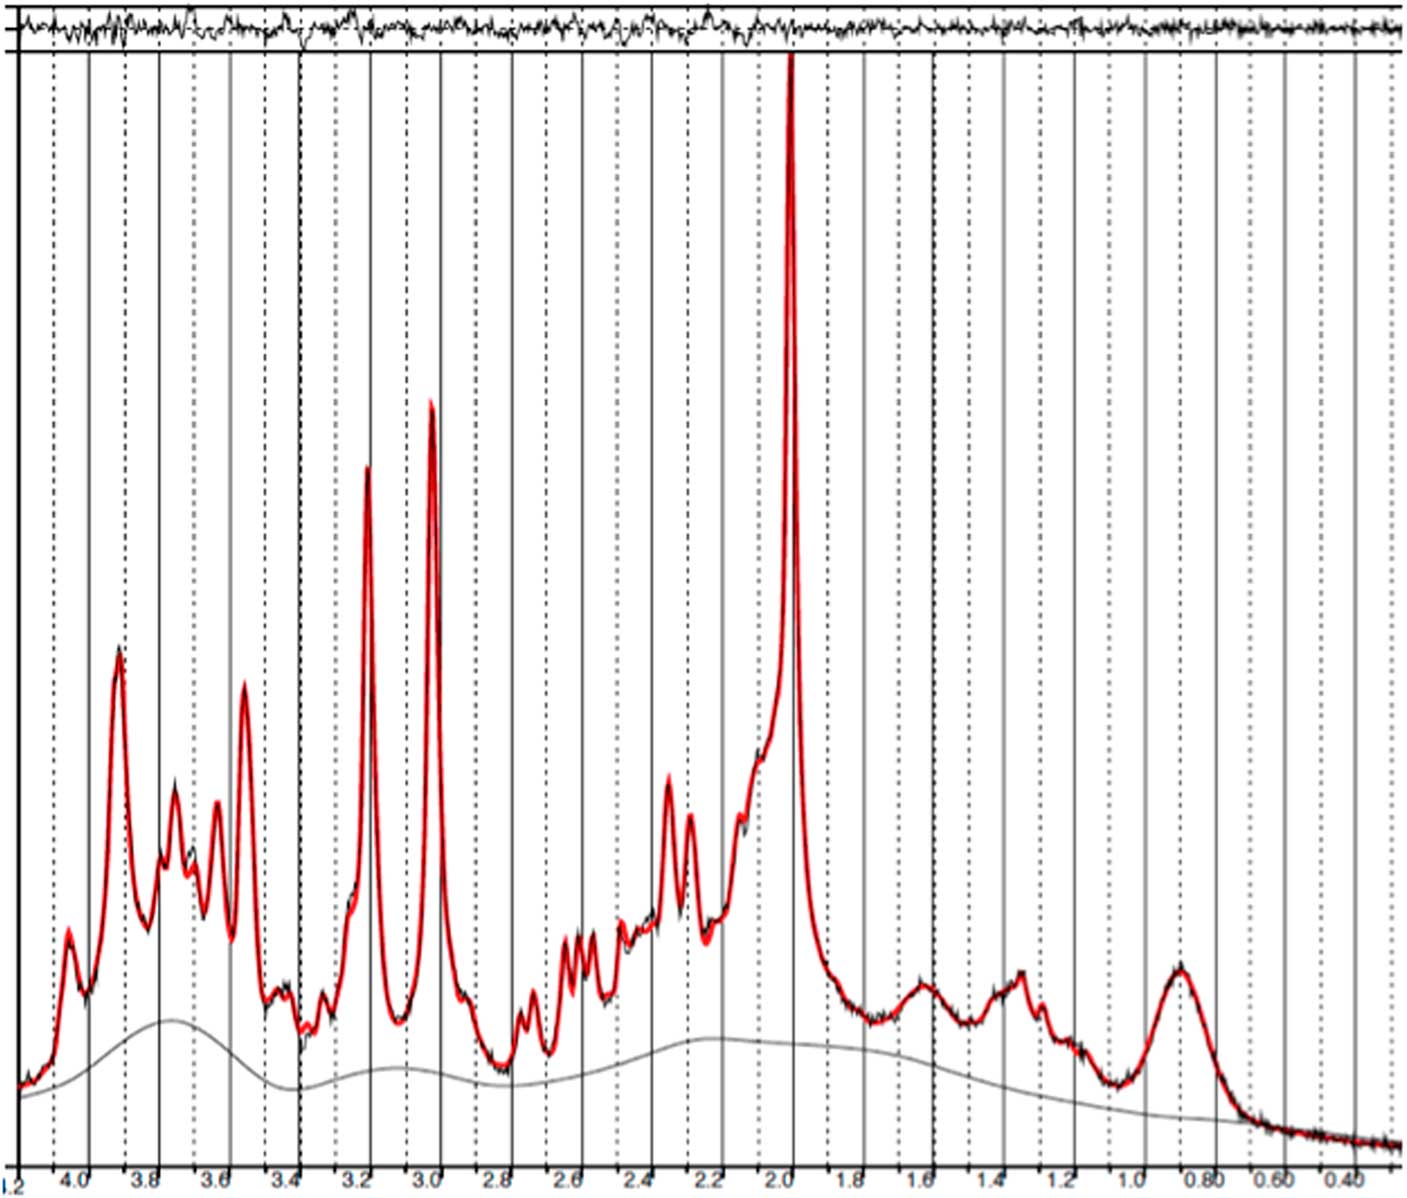

Baseline and follow-up data were collected from all 11 patients. However, prefrontal spectra from one patient (male) and one healthy subject (male) were discarded due to poor quality (CRLB>20%). Figure 2 illustrates representative spectra from PFC and Fig. 3 an individual plot for the GABA signal in PFC. No significant difference in prefrontal GABA levels was observed between patients pre-ECT (mean 0.248±0.04) and healthy subjects (mean 0.249±0.03), t(20)=0.089, p=0.93 (Fig. 4). To examine whether GABA/Cr ratios were affected by changes in creatine, we tested for significant differences in GABA/NAA ratios (p=0.92) and NAA/Cr ratios (p=0.99), but no significant difference was found. Diagnosis, that is bipolar disorder or MDD did not interact significantly with the GABA/Cr ratio (p=0.75). Moreover, we found no significant changes in GABA/Cr ratio after excluding patients receiving benzodiazepines.

Fig. 2 Example of a representative spectrum from the prefrontal cortex. The raw data are plotted as a thin black curve. The thick red curve is the LcModel fit to this data. The baseline is also plotted as a thin black curve. At the top are plotted the residuals.